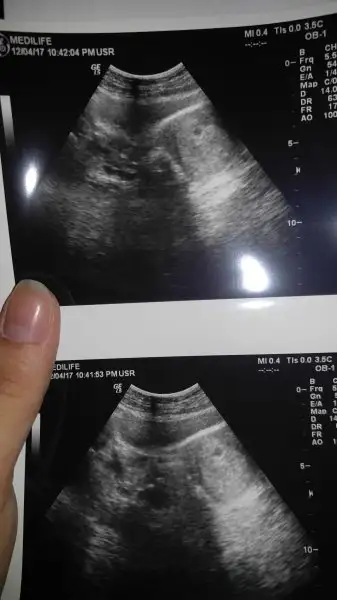

Bnce sağdaki minicik sey benim de ilk gördüğümde öyleydi ama doktor üstünü işaretledi ben öyle gördümKızlar selam. Sat 4 mart. Daha önce keseyi görmedik. Bugün açık kahverengi lekelenmem oldu doktora gittim. Doktor kesemiz burada dedi. Görüyorum dedi. Fakat hangisi kese ben anlamadım. Sağdaki minicik yuvarlak şeymi yoksa soldaki hafif yatay şeymi anlamadım :)

Super anneler 2017 topigindeki kizlar bu isten baya iyi anliyo istersen oraya yolla resmi cvp verirler. Hayırlı olsun.Kızlar selam. Sat 4 mart. Daha önce keseyi görmedik. Bugün açık kahverengi lekelenmem oldu doktora gittim. Doktor kesemiz burada dedi. Görüyorum dedi. Fakat hangisi kese ben anlamadım. Sağdaki minicik yuvarlak şeymi yoksa soldaki hafif yatay şeymi anlamadım :)

Soldaki siyah duran canımKızlar selam. Sat 4 mart. Daha önce keseyi görmedik. Bugün açık kahverengi lekelenmem oldu doktora gittim. Doktor kesemiz burada dedi. Görüyorum dedi. Fakat hangisi kese ben anlamadım. Sağdaki minicik yuvarlak şeymi yoksa soldaki hafif yatay şeymi anlamadım :)